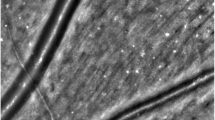

Following full pupil dilation, first the monochromatic (red-free) and after a resting period of a minimum of 5 min the oximetry (dual-wavelength) retinal photographs were obtained using a Zeiss FF450+ fundus camera (Zeiss, Germany and Imedos Systems, Germany) with the optic nerve head (ONH) centred and the camera field angle set to 30° (see sample image and measurement area in Fig. 1). One image obtained with the dual wavelength filter (specifications: 548 ± 10 nm (full width at half maximum) and 610 ± 10 nm) and one monochromatic image were used to measure the CRAE and CRVE of each image; more detail on the spectral transmission of the dual wavelength filter used for retinal oximetry can be found elsewhere [9]. Room illumination was switched off during imaging.

In brief, retinal vessel diameters were measured using a semi-automated piece of software (VesselMap 2, Imedos, Germany) by a single observer (OS). Following image selection, two concentric rings with ½ Disc Diameter (DD) and 1 DD were placed distant from the ONH. The same vessels were assessed in both images. The six largest retinal arteries and veins passing through the ring segment (see Fig. 1) were included in the analysis as recommended by Knudtson and colleagues [2]. The formulae used to derive CRAE and CRVE after three iterations are provided in Eqs. 1, 2 (Parr-Hubbard method)1 below: